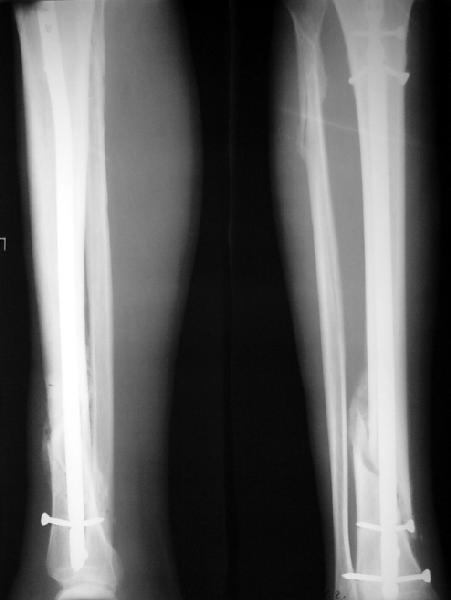

На мой взгляд, на снимках, приведённых Вами - неправильно сростающийся перелом дистальной трети большеберцовой кости, состояние после остеосинтеза интрамедуллярным гвоздём.

Как Вы пишите снимок под номером 1 - менсяц после операции, под номером 2- два месяца после операции.

I think that the X-Rays show S/P IMN of Spiral # of the Distal Tibia consoles in misalignment.

You wrote that a picture number 1 - f month after the surgery, and number 2-two months after the surgery.

Ok. А также и следующий, в 3 месяца.